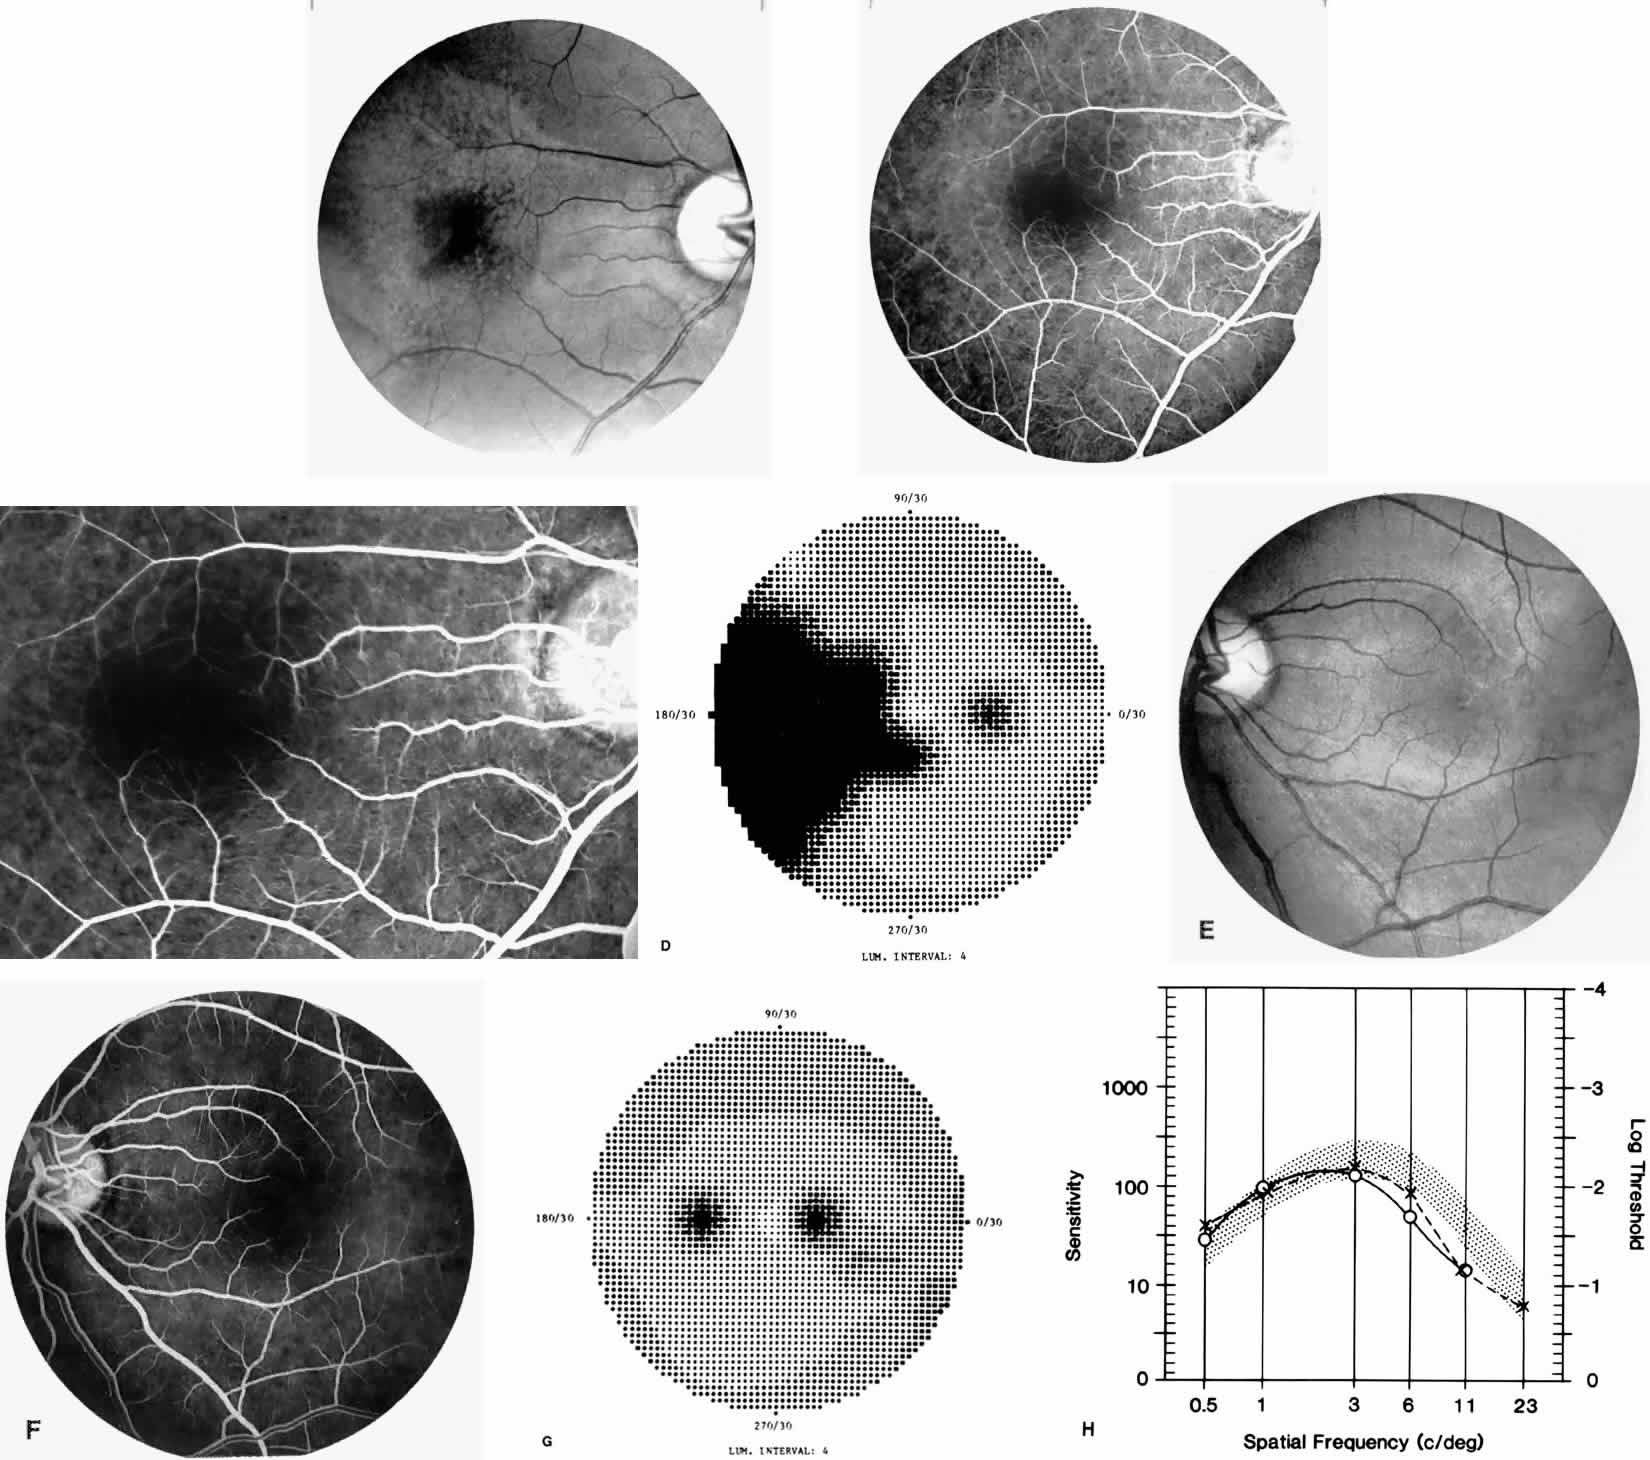

Occlusions of the fine vasculature of the macular and perimacular area have been reported in 10% to 40% of patients with sickle cell disease.18,83,91–99 In the acute phase, the occluded vessel will have a dark red appearance and may appear as a dark line on fluorescein angiography (Fig. 9). Nerve fiber layer infarcts (cotton-wool spots) are seen (see Fig. 8D and E;Fig. 10).100

Other macular and perimacular changes include microaneurysm-like dots, dark and enlarged segments of arterioles, hairpin-shaped venular loops, pathologic avascular zones, and widening and irregularities of the foveal avascular zone (Figs. 11 and 12). In the Jamaican cohort study evaluating children with homozygous sickle cell anemia and SC disease between the ages of 5.0 and 7.5 years of age, no pathologic avascular zones could be identified despite a high incidence of peripheral vascular closure.31 In evaluating patients with homozygous sickle cell anemia, no relationship between ISC counts and macular abnormalities or visual acuity could be found.101 Using fluorescein angiography, investigators have found the foveal avascular zone to be significantly larger in eyes with clinical evidence of sickle cell maculopathy as compared with normal eyes and eyes without clinical evidence of sickle cell maculopathy.102–104

Careful examination by fluorescein angiography, looking for areas of capillary dropout and other capillary abnormalities, is often necessary to identify the macular changes. These changes may be transient, and the macula may appear normal on subsequent fluorescein angiograms (Fig. 13). Although fluorescein angiography may or may not demonstrate reperfusion of a previously occluded capillary bed, a loss of the inner retinal layers results in an ophthalmoscopic focal concavity with an abnormal reflex (retinal depression sign) (see Fig. 8E).105,106 These changes are usually permanent. The retinal depression sign is not pathognomonic of sickle cell disease and may be seen with other arteriolar occlusive diseases, such as embolic retinopathy, vasculitis, and hypertension.

Macular Function Testing in Sickle

Cell MaculopathyThe visual acuity in patients with sickle cell disease is often normal, despite the presence of an enlarged foveal avascular zone or other evidence of sickle cell maculopathy (Fig. 14). In addition, patients with sickle cell maculopathy have a remarkable absence of visual complaints. Although 55% of patients with homozygous sickle cell anemia had abnormal contrast sensitivity, no significant relationship was demonstrated between contrast sensitivity and macular vascular abnormalities.101 Automated visual field analysis has demonstrated significantly larger scotomas in patients with abnormally enlarged foveal avascular zone.102 Color vision testing has revealed a greater incidence of blue-yellow defects in patients with sickle cell retinopathy; however, no significant correlation has been demonstrated between color vision defects and the presence of sickle cell maculopathy.98,107